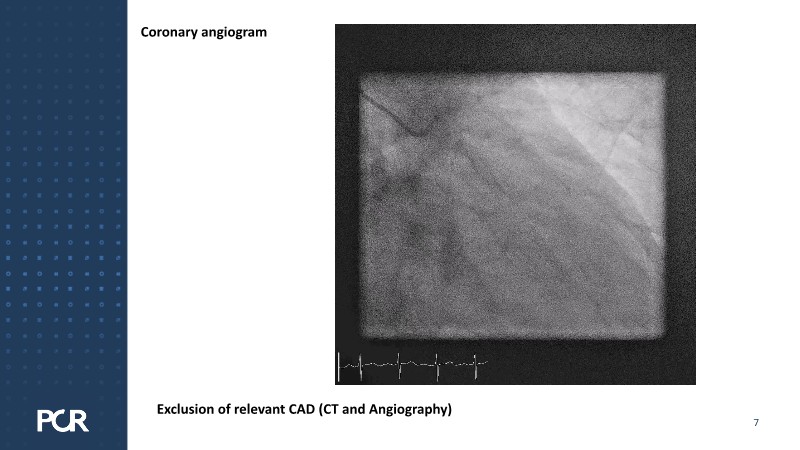

This session examines these crucial aspects through the case of a 77-year-old male with bicuspid aortic valve stenosis, HFpEF and multiple comorbidities, including diabetes, obesity and sleep apnoea.